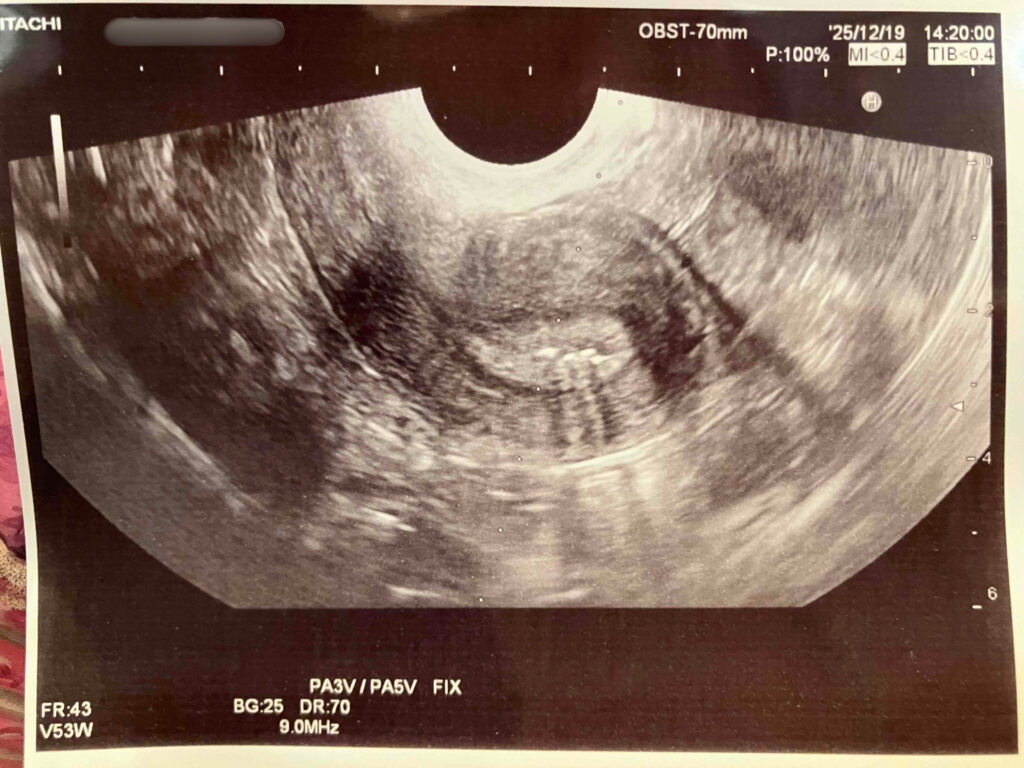

天井近くのモニターには、今日移植する胚盤胞が映し出されていて、雪だるまのような可愛らしい形。本日移植するのは、3つ凍結できたうちの1番グレードがよかった5ABの子。

培養士さんがカテーテルで胚盤胞を吸い上げ、「これから子宮の中に入れていきますね」と説明してくれました。

そして最後に、「入ったところが白く光りますよ」と聞いていた通り、本当にキラッと光った瞬間が見えて…思わず感動。

終了後、看護師さんからエコー写真を手渡してもらい、ここでもまた感動(感動②)。